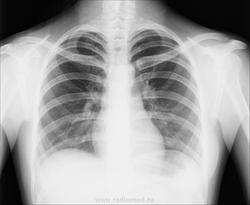

Женщина, 30 лет. Профилактическое обследование. Тени на верхушке справа. Tbs? или тень складки. ID:47186 Чт, 06/03/2014 - 15:54 #1 Сергей Кузьминов Не на сайте Был на сайте: 1 год 1 неделя назад Зарегистрирован: 06.10.2012 - 15:51 Публикации: 11813 Как-то норма. Чт, 06/03/2014 - 17:56 #2 NIL Не на сайте Был на сайте: 18 часов 22 минуты назад Зарегистрирован: 25.11.2013 - 20:50 Публикации: 18205 Норма. "Слушай всех, прислушивайся к немногим, решай сам".© Чт, 06/03/2014 - 18:38 #3 И.Бондаренко Не на сайте Был на сайте: 3 дня 11 часов назад Зарегистрирован: 13.09.2011 - 22:55 Публикации: 9206 Сергей Кузьминов wrote: Как-то норма. +1. Это тень мягких тканей шеи накладывается. Чт, 06/03/2014 - 19:21 #4 Dima Не на сайте Был на сайте: 7 лет 2 месяцев назад Зарегистрирован: 05.08.2012 - 17:39 Публикации: 2467 И.Бондаренко wrote: Сергей Кузьминов wrote: Как-то норма. +1. Это тень мягких тканей шеи накладывается. Грудино-ключично-сосцевидная мышца, по-всей видимости. Терпимость - это когда прощают чужие ошибки; такт - когда не замечают их. (Артур Шницлер) Чт, 06/03/2014 - 20:30 #5 выпускник Не на сайте Был на сайте: 5 лет 4 недели назад Зарегистрирован: 15.08.2012 - 23:11 Публикации: 50 тени, подозрит. на тбц? Чт, 06/03/2014 - 22:17 #6 Андрей Юрьевич Не на сайте Был на сайте: 4 дня 15 часов назад Зарегистрирован: 16.11.2008 - 22:16 Публикации: 18098 По сокрашениям: не tbs, a tbc (от TuBerCulosis). Андрей Юрьевич Чт, 06/03/2014 - 22:35 #7 Дмитрий Волегов Не на сайте Был на сайте: 3 года 6 месяцев назад Зарегистрирован: 22.05.2013 - 00:32 Публикации: 1148 Повернуть бы на скопии ещё немного правым боком вперед и успокоиться. С Уважением, Дмитрий. Чт, 13/03/2014 - 07:46 #8 Лейман Иван Не на сайте Был на сайте: 2 месяцев 2 дня назад Зарегистрирован: 09.01.2014 - 07:54 Публикации: 1190 Да вроде норма. Чт, 13/03/2014 - 08:52 #9 Катенёв Валенти... Не на сайте Был на сайте: 7 лет 2 недели назад Зарегистрирован: 22.03.2008 - 22:15 Публикации: 54876 Ёлка wrote: Tbs? или тень складки. Так если подозрения возникли, так верхушку срезать надо, к примеру, на восьмерке.

+1. Это тень мягких тканей шеи накладывается.

тени, подозрит. на тбц?

По сокрашениям: не tbs, a tbc (от TuBerCulosis).

Повернуть бы на скопии ещё немного правым боком вперед и успокоиться.

Так если подозрения возникли, так верхушку срезать надо, к примеру, на восьмерке.